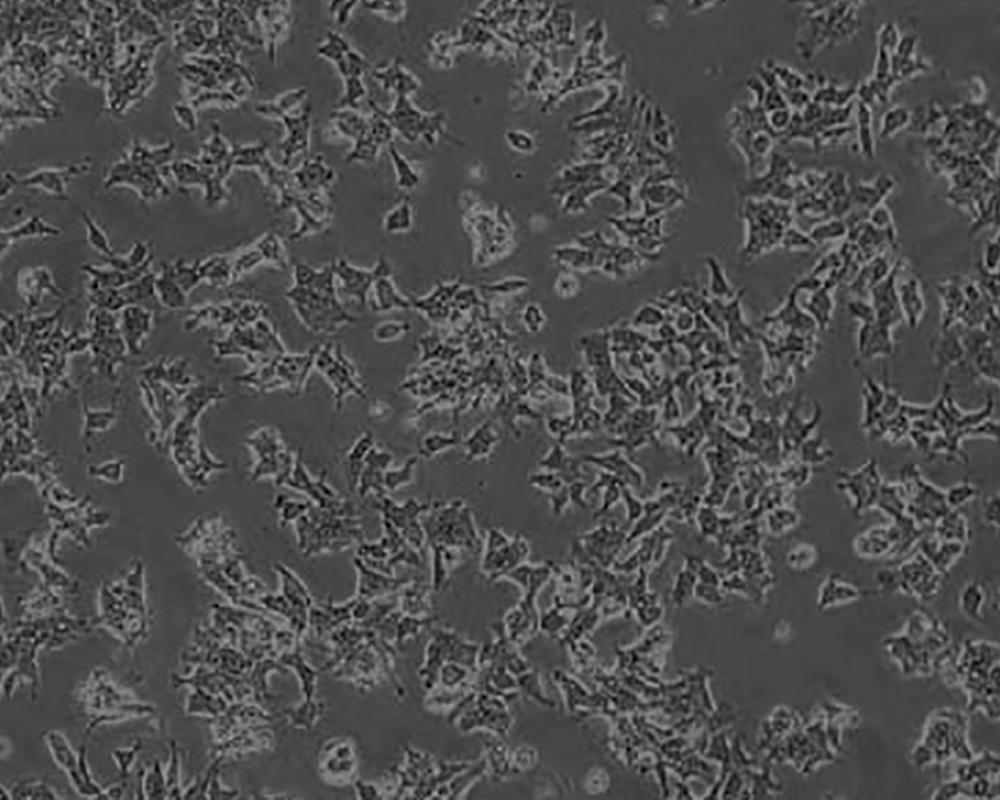

22RV1(22-RV1,22RV1)細胞

產品名稱 22RV1(22-RV1,22RV1)細胞

中文名稱 人前列腺癌細胞

組織來源 前列腺癌;男性

生長特性 adherent

形態特征 epithelial

細胞描述 22RV1是來自異種移植(在閹割引起前列腺癌衰退又在其父親的雄性激素信賴型CWR22嫁接后復發的小鼠中連續傳代)的人前列腺癌上皮細胞系。此細胞系表達前列腺特異抗原。二羥基睪丸脂酮輕微刺激細胞生長,經westernblot檢測溶解產物與抗雄性激素受體抗體起免疫反應。EGF刺激細胞生長,但TGFβ-1不能抑制細胞生長。該細胞在裸鼠中成瘤。